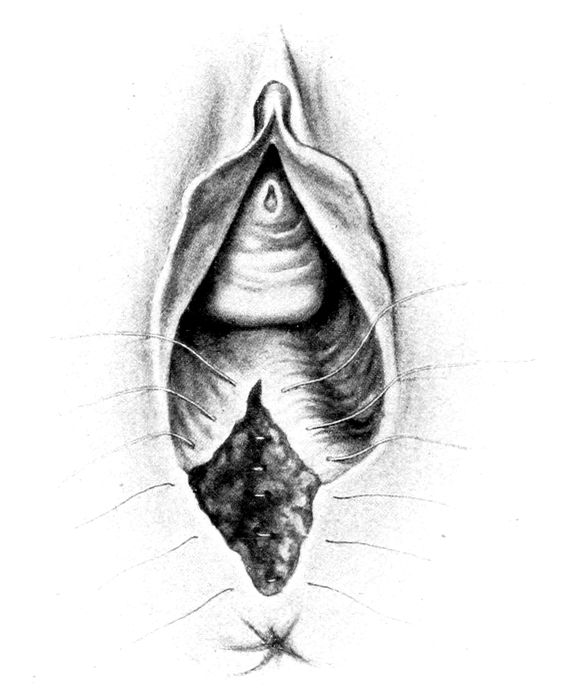

| 92. |

Episiotomy |

212 |